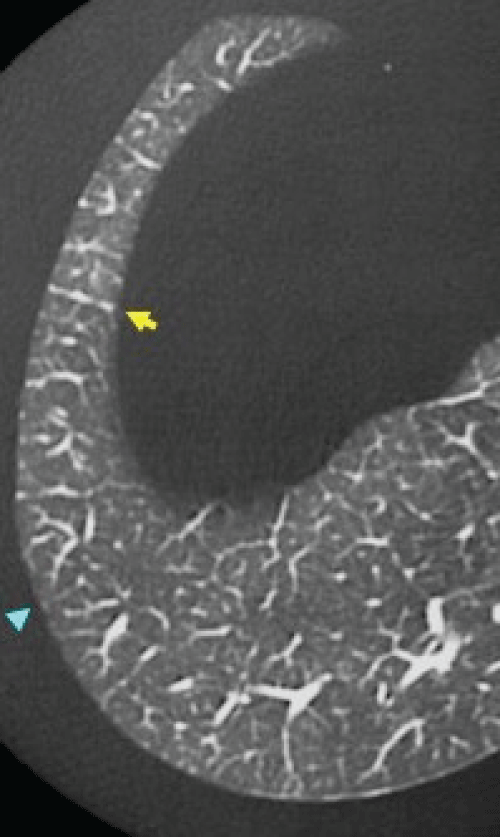

Radiological findings: Chest high resolution computed tomography (HRCT) findings without contrast material were reviewed. These images comprised 1.5 mm collimation sections at 10 mm intervals. We evaluated the presence of consolidation, ground-glass opacity, reticular opacity, traction bronchiectasis and lung tip consolidation at below 1 cm of right diaphragm. Definition of ground-glass opacity was hazy increased attenuation of the lung that did not obscure the underlying vessels. Consolidation was defined as homogeneous increase in pulmonary parenchymal attenuation that obscured the underlying vessels. Definition of reticular opacity was regular interlacing linear shadows separated by a few millimeters. Traction bronchiectasis was defined as Irregular bronchial dilatation within or around areas with parenchymal abnormality. Definition of lung tip consolidation was thick consolidation > 3 mm with connection of both right diaphragm and pleura. Extent of consolidation, ground-glass opacity, reticular opacity, traction bronchiectasis was defined as follows; 0: none, 1: < 25%, 2: 25% < 50% >, 3: 50% < 75% >, 4: > 75% [20]. Extent of lung tip consolidation was defined as 0: none, 1: one thick consolidation, 2: more than two thick consolidations. Thick was defined over 3 mm. Lung tip consolidation looks like migratory bird. Therefore, we call it migratory bird sign. The score of each finding was defined as total sum divided into patient's number.

Figure 1 Representative image of Lung Tip consolidation.

Arrow indicates two thick consolidation and migratory birds sign.

In PFT, PM-ILD patients tended to show decreased %FVC, TLC and % DLco (71.4 vs. 78.3, 84.6 vs. 90.9, 65.6 vs. 94.8), however, it did not show statistically significance (Table 4). In terms of radiological findings, DM-associated ILD patients showed more lung tip consolidation than PM-ILD patients. (0.44 vs. 0.11, p = 0.025) (Table 5). Among five CADM-associated ILD patients, 80% of the patients had lug tip consolidation, on the other hand, 14% of the PM-ILD patients and 43% of the DM-associated ILD patients had lung tip consolidation. Representative image of lung tip consolidation is shown in figure 1. We call this finding migratory bird sign. Regarding treatment, 39 patients received high dose prednisolone initially. Especially, we did steroid pulse with immunosuppressants such as cyclosporine or tacrolimus for CADM associated ILD patients. In maintenance phase, PM-associated ILD patients more often took prednisolone alone (54.5% vs. 33.3%) and DM-ILD patients received more prednisolone plus tacrolimus (38.9% vs. 9.1%). Among the four anti-MDA-5 antibody positive patients, three patients (75%) died finally despite intensive therapy. Kaplan-Meier survival curve showed DM associated ILD group showed poor prognosis compared with that of PM related ILD group (88.6 months vs. 44.7 months, p = 0.009) (Figure 2). Overall, ten patients died during observation period. Cox proportional hazard model showed Gottron sign, subungual erythema, lung tip consolidation, diagnosis of DM and Anti-MDA-5 antibody[hazard ratio(HR); 7.33: p = 0.020, HR; 8.78: p = 0.004, HR; 2.494: p = 0.042, HR; 6.343: p = 0.021, HR; 25.76: p = 0.001, respectively]were strong predictors of PM/DM associated ILD patients at our cohort (Table 6).

In terms of radiological findings, chest HRCT is crucial for evaluation of CTD-ILD. Among PM/DM patients, interstitial changes are frequently located in bilateral lower lobes [33,34]. GGO, consolidation, reticular opacity, traction bronchiectasis and linear opacities are frequent HRCT findings of PM-DM ILD. Linear opacity was found all our PM/DM ILD patients. Therefore, we thought this may not be possible prognostic discriminator and excluded our analysis. In Anti-ARS syndrome often have volume loss of lower lung field and peri-bronchovascular consolidation [31]. These HRCT findings correspond pathologically to organizing pneumonia (OP) or non-specific interstitial pneumonia (NSIP) or variant of organizing pneumonia with supervening fibrosis [35,36]. GGO and reticulation correspond to reversible fibrosis. We focused on lung tip consolidation. Because such findings were often seen in our CADM associated ILD. On the other hand, this consolidation was not detected in normal population (Figure 3). We think grade of lung tip consolidation was rather mild in PM-associated ILD patients. Therefore, more extensive lung tip consolidation of CADM patients caused strong limitation of movement of diaphragm and overall lower lung field. With these findings, we provide more intensive treatment immediately. We built up hypothesis that these lung tip consolidation or migratory bird sign may limit the movement of right diaphragm. In addition, there are more gravity dependent and more respiratory movement for removal of exudates in this extreme basal area. If persistent inflammation or fibrosis continue in this area, this will lead to severe restrictive disorder or profound dyspnea. Our study showed lung tip consolidation predicted mortality of CADM associated ILD patients. Therefore, our proposed hypothesis might be correct.